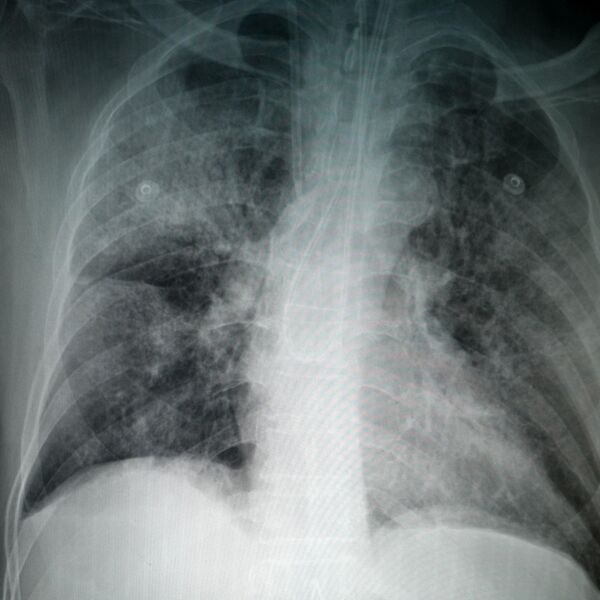

"Postoje situacije u kojima određeni pacijenti, iako su bili na kućnom lečenju i nisu imali ono što zovemo virusna upala pluća i neki oblik respiratorne infekcije, traže pomoć lekara", kaže dr Nataša Petrović Stanojević, pulmolog u KBC Zvezdara.

Simptomi takozvanog produženog kovida najčešće traju od dve do osam nedelja, kažu lekari. Ukoliko se javljaju i kasnije, pacijent treba da se obrati izabranom lekaru kako bi se obavila detaljna ispitivanja.